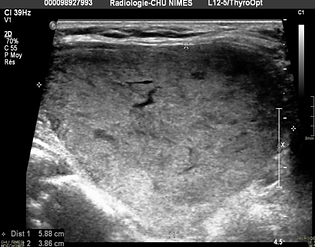

Paciente de 57 años con nódulo en lóbulo derecho, gen local, benigno en citología, evaluación biológica normal, rechazo a cirugía

Antes del tratamiento